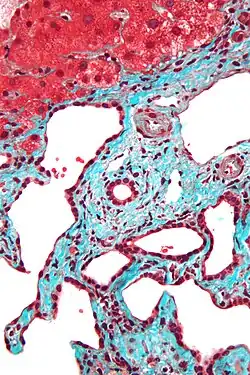

Micrograph of a bile duct hamartoma. Trichrome stain. Intermediate magnification

-